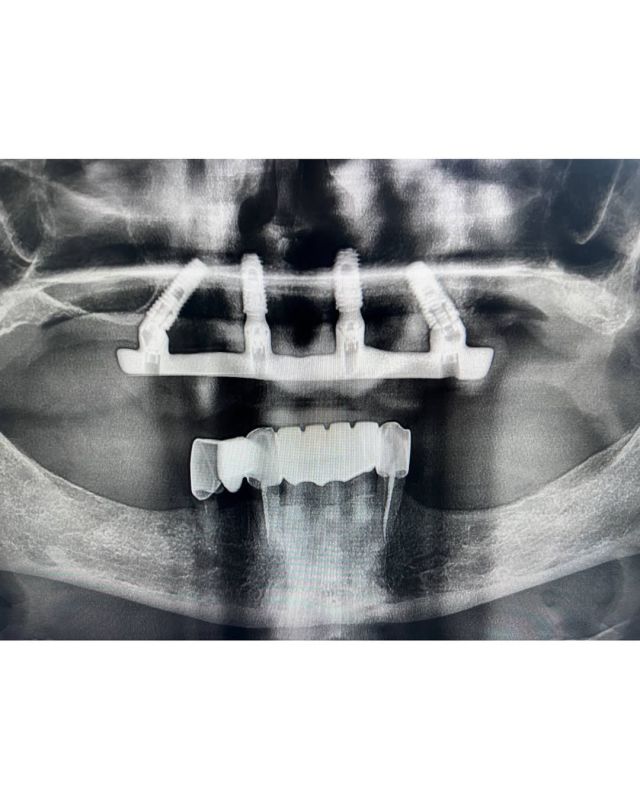

Без костной пластикиЗубы за 1 день Одномоментная имплантация Имплантация с нагрузкой Коронка на импланте

Клинические случаиИмплантация All-on-4 Имплантация All-on-6 Имплантация All-on-8 Синус-лифтинг